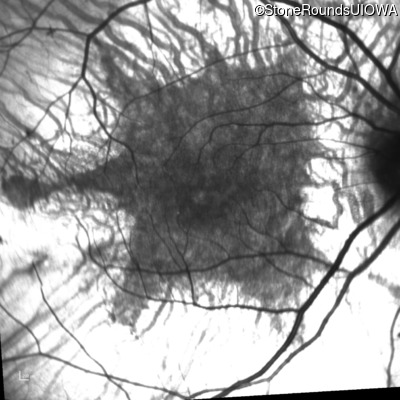

Infrared Fundus Photograph - Right - 20/32

Exemplar